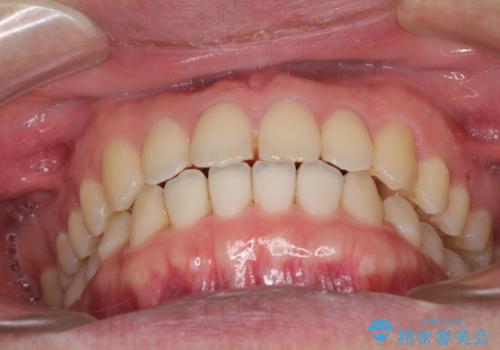

すきっ歯の改善 インビザライン矯正治療

- 上の前歯の隙間を気にして来院された患者様です。

インビザラインにより、上下の歯列を側方に拡大しつつ、前歯の隙間を閉じていくこととしました。

1日22時間の装着時間をしっかりと守ってくださったので、隙間がきれいに閉じ、口元の突出感も改善することができました。